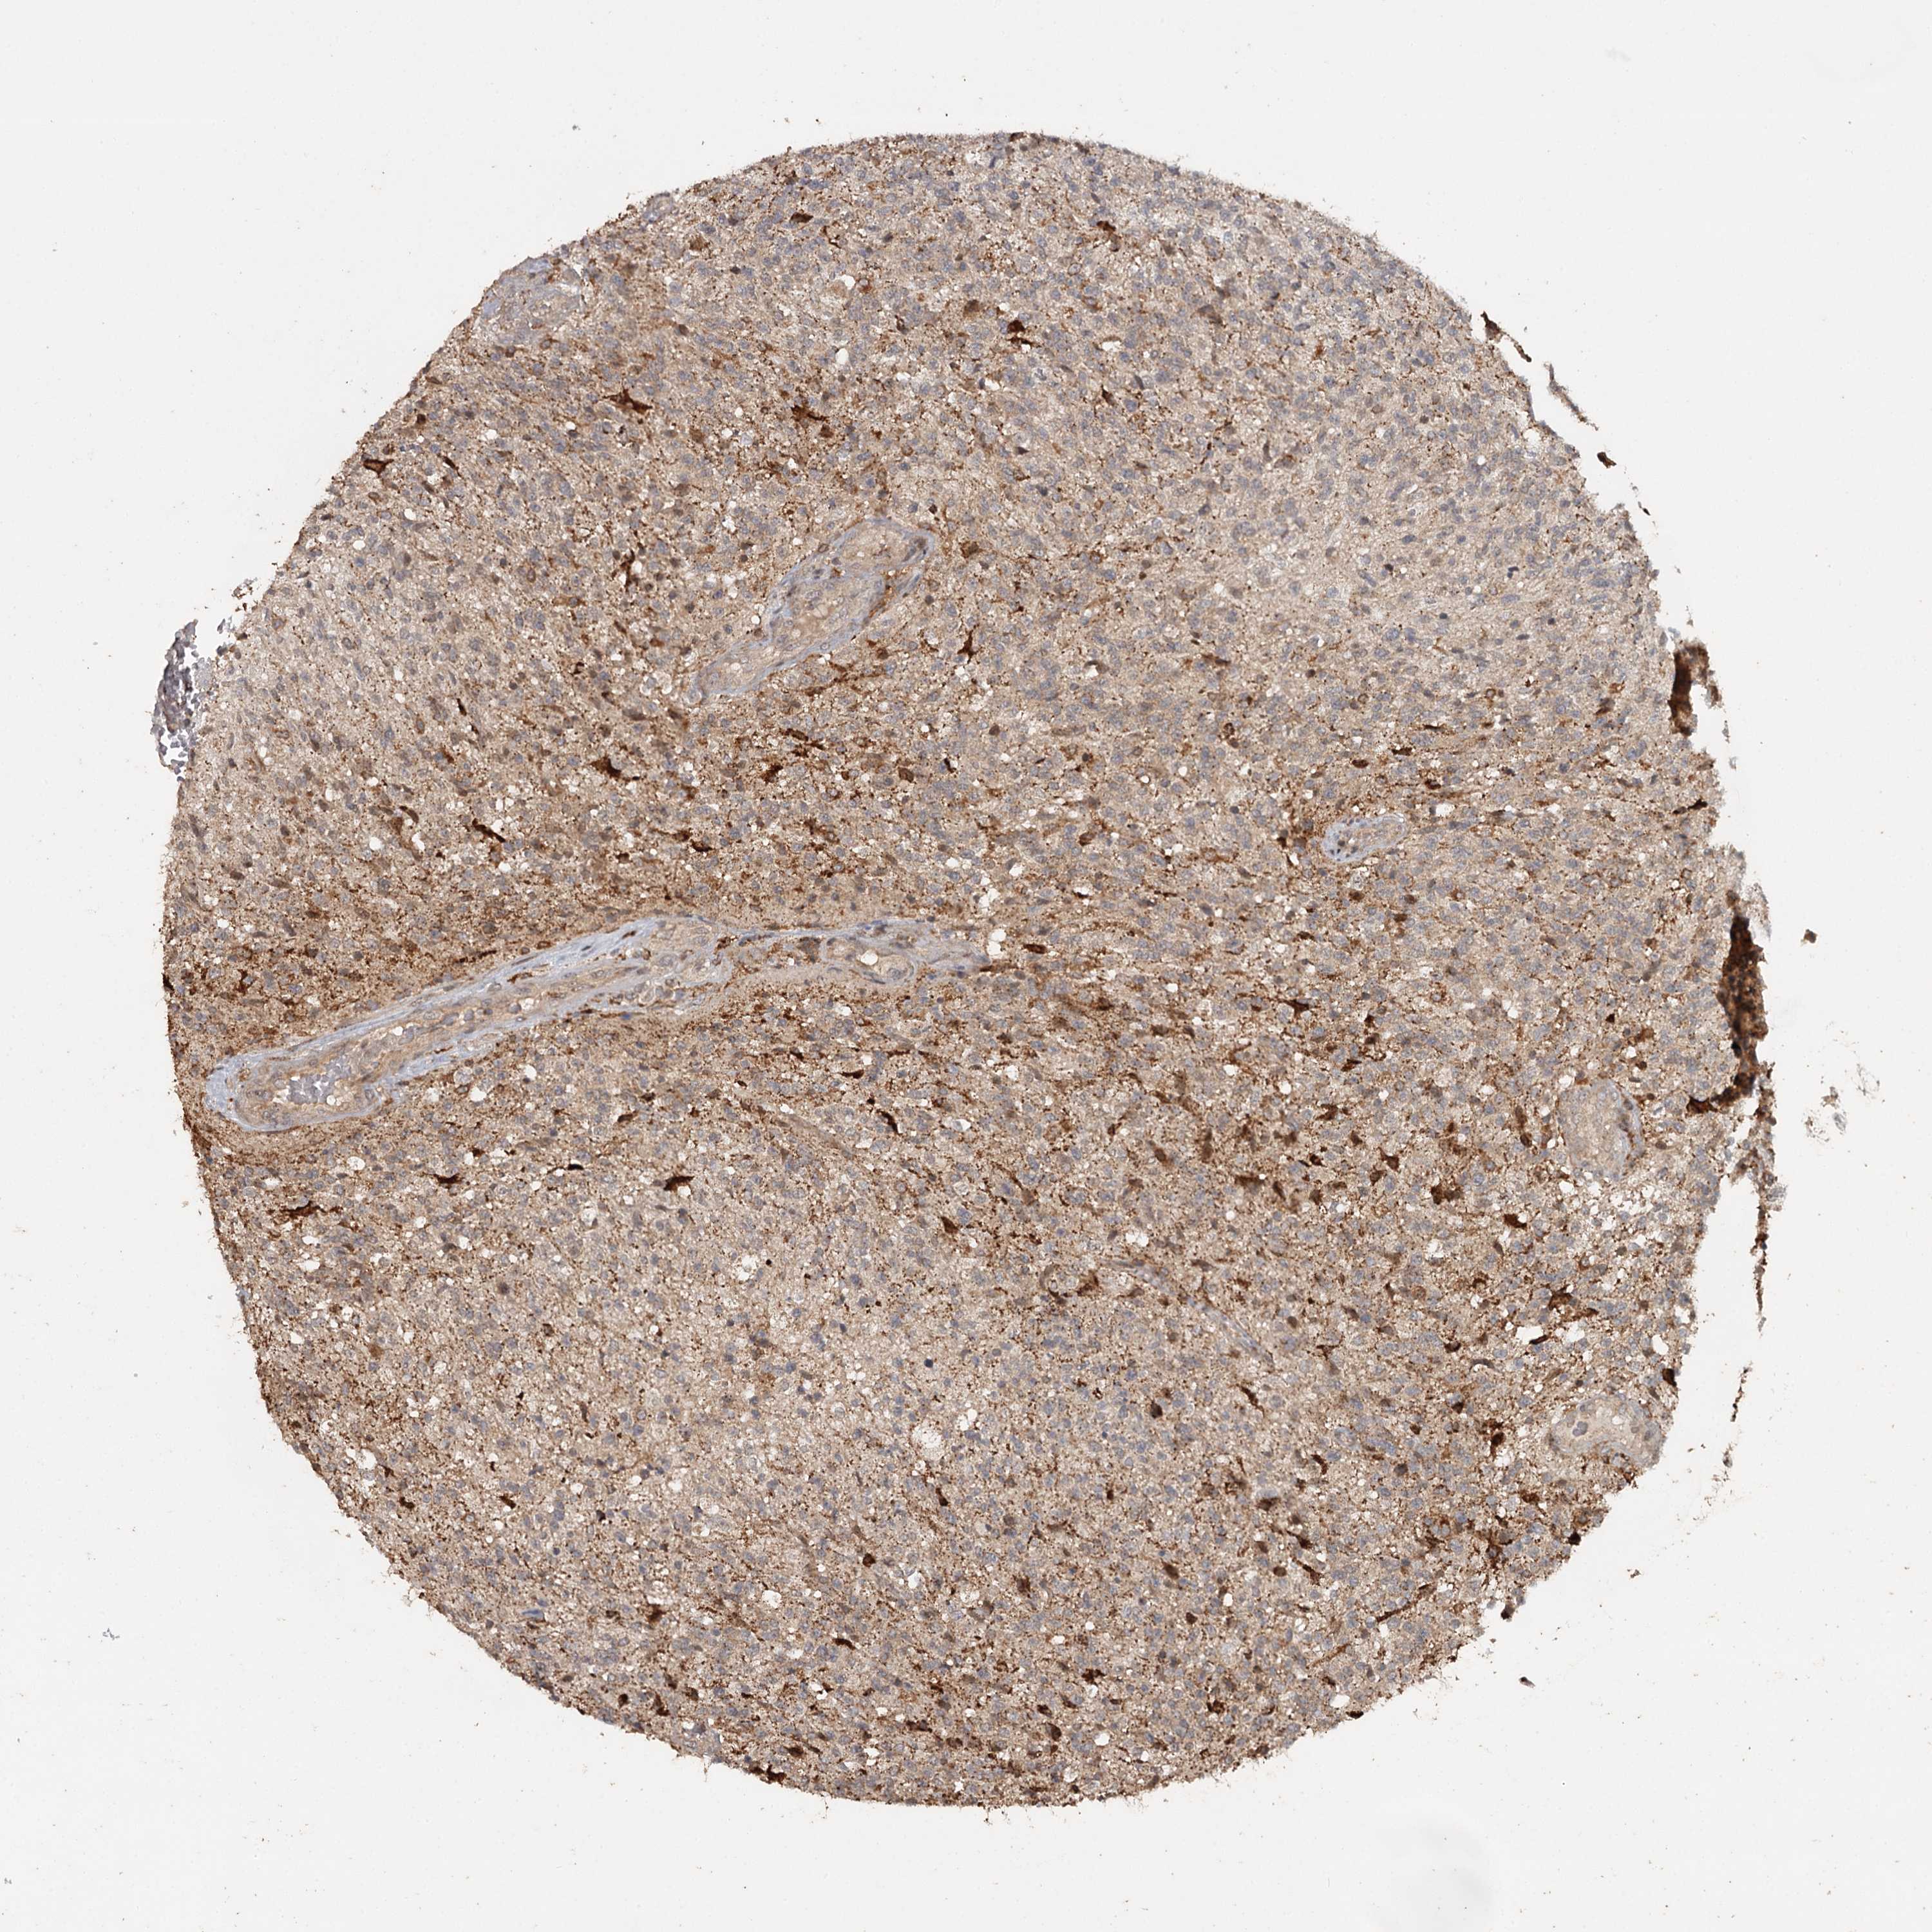

GLIOMA - Protein expressioni

A mouse-over function shows sample information and annotation data. Click on an image to view it in a full screen mode. Samples can be filtered based on level of antibody staining by selecting one or several of the following categories: high, medium, low and not detected. The assay and annotation is described here.

Note that samples used for immunohistochemistry by the Human Protein Atlas do not correspond to samples in the TCGA dataset.

Antibody stainingi

Antibody staining in the annotated cell types in the current human tissue is reported as not detected, low, medium, or high, based on conventional immunohistochemistry profiling in selected tissues. This score is based on the combination of the staining intensity and fraction of stained cells.

Each image is clickable and will lead to virtual microscopy that enables deeper exploration of all samples and also displays staining intensity scores, fraction scores and subcellular localization as well as patient and tissue information for each sample.

Antibody HPA039106

Staining

High

Medium

Low

Not detected

Intensity

Strong

Moderate

Weak

Negative

Quantity

>75%

75%-25%

<25%

None

Location

Nuclear

Cytoplasmic/membranous

Cytoplasmic/membranous,nuclear

Glioma, malignant, High grade

Glioma, malignant, Low grade

Glioblastoma, NOS